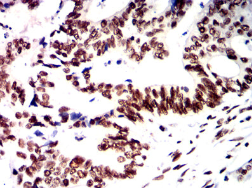

IHC    1/200-1/1000